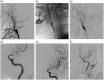

Figures